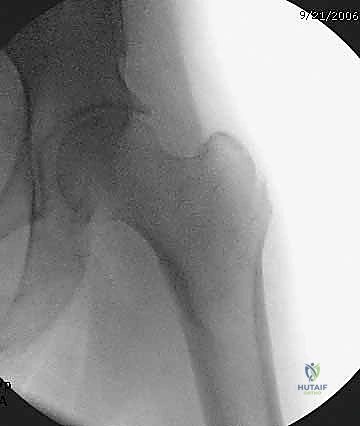

التصوير الطبي المتقدم

- الأشعة السينية (X-rays): هي المعيار الذهبي الأولي. يتم أخذ صور من الأمام للخلف (AP) وصور جانبية (Lateral) للحوض والورك المصاب. تكشف هذه الصور عن موقع الكسر، نوعه (بسيط أم مفتت)، ودرجة الإزاحة.

- التصوير المقطعي المحوسب (CT Scan): في الحالات المعقدة، أو عندما يكون الكسر مفتتاً بشدة ويمتد إلى مناطق أخرى، يطلب الدكتور هطيف صورة مقطعية ثلاثية الأبعاد لبناء خطة جراحية دقيقة للغاية.